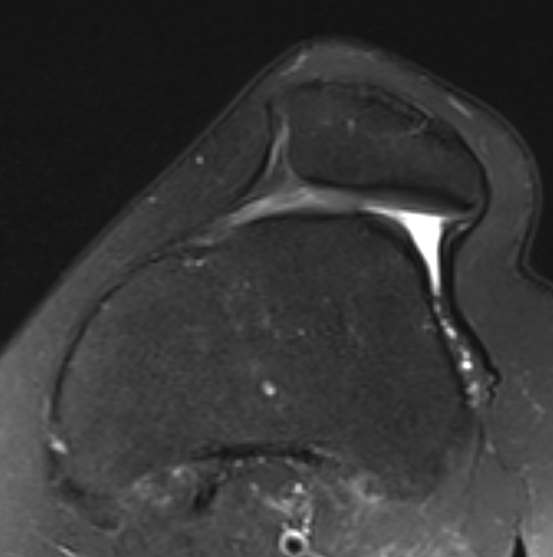

MRI

Lateral subluxation / trochlea dysplasia

Articular cartilage damage

TTTG